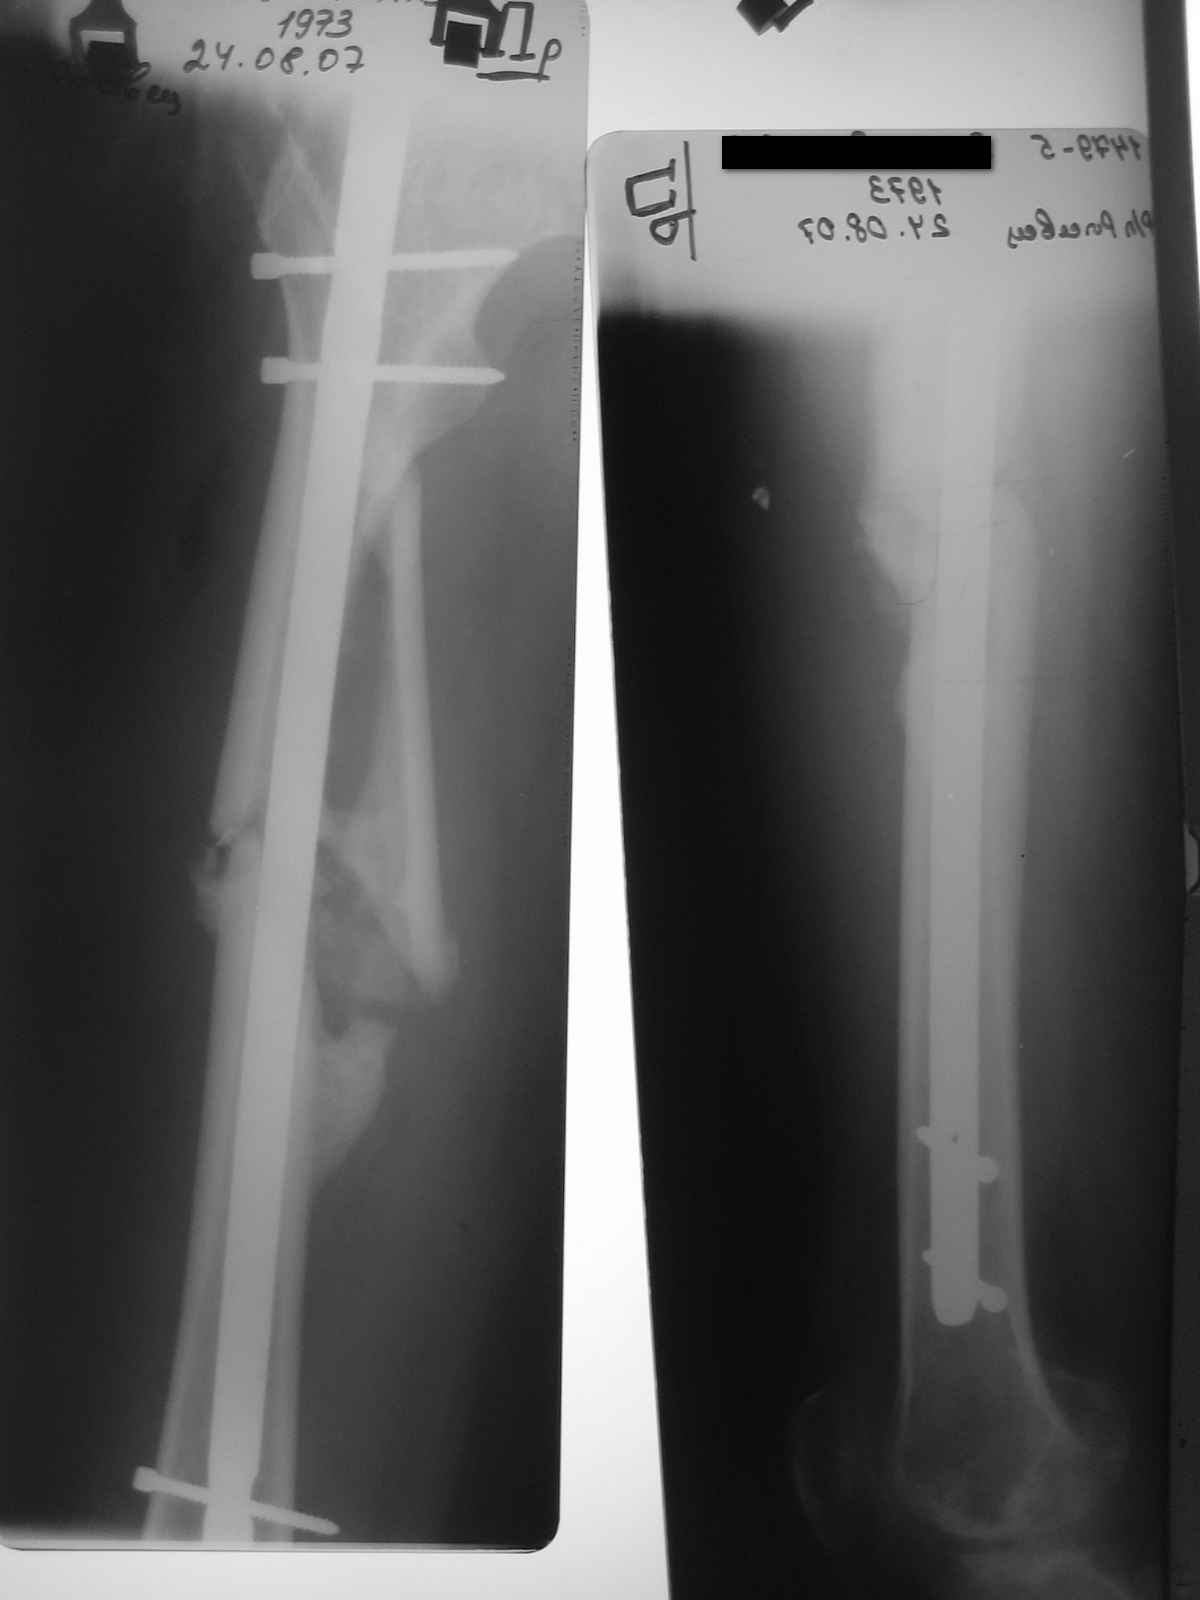

затем гипс еще 1,5 месяца, дозированная нагрузка через 3,5 месяца после травмы. Дней 5 назад поскользнулся в ванной, почувствовал боль в бедре, появилась деформация. Оперирован у нас, произведен остеосинтез блокирующим стержнем ,перелом не открывался, был "доломан" на столе. меня интересует вариант вальгирования гвоздя в этом случае. И по-вашему какие ерспективы у этого клиента?

Учитывая отсутствие медиальной стенки на большом протяжении, действительно, мог быть варус при латеральном заходе. Но удалось вполне неплохо справиться, можно поздравить. Из дополнительных мер - точку входа надо делать чуть медиальнее, и можно ввести спицу спереди назад над дефектом, чтобы гвоздь оттеснить к латеральной стенке канала.

А перспектива - самая благоприятная, пусть пока коленом занимается форсированно, если не успел к этой травме восстановить движения полностью